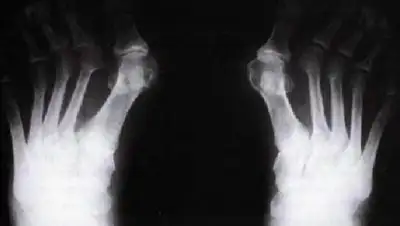

По материалам гражданского дела, 16 января 2014 года  женщина вывихнула второй палец левой стопы.  Она обращалась к народным целителям, которые вправляли ей вывих. В больницу женщина обратилась не сразу, а лишь 26 февраля, чтобы проверить на рентгене результат народного целительства. Снимок показал, что вывих не вправлен.  На следующий день была проведена  операция по вправлению вывиха, приведшая   через некоторое время к печальным последствиям – ампутации пальца.